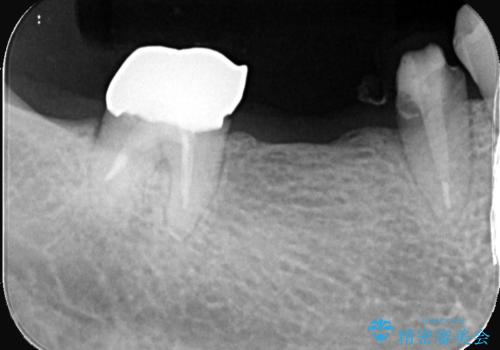

両支台歯が失活歯のため、どちらかもしくは両方の歯が破折した際、再度ブリッジを除去した治療が必要になるリスクとインプラント治療のご提案もさせていただきましたが、ブリッジでの治療を希望されました。

右下5番は支台歯CR築造を行っています。